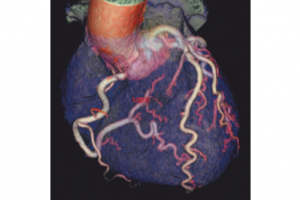

Система Optima CT660 предлагает новейшие достижения компьютерной томографии, удобство использования и широкие возможности применения в таких областях, как кардиология, онкология, сосудистая визуализация, а также динамическая визуализация.

Система Optima CТ660 помогает врачам-радиологам проводить широкий спектр эффективных исследований в условиях оптимизированной лучевой нагрузки:

При исследовании сердца высокая скорость оборота гентри обеспечивает превосходное временное разрешение (44 мс).